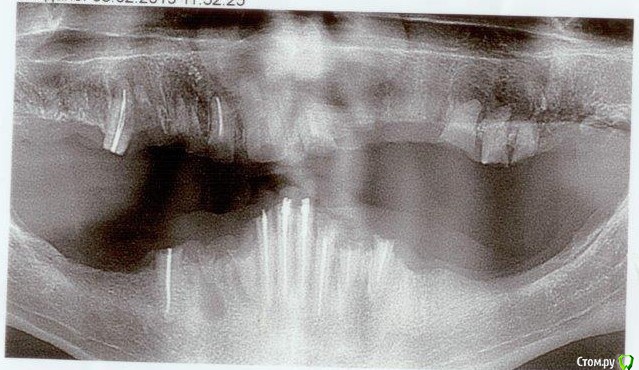

Mapcuk Опубликовано 26 марта, 2019 Поделиться Опубликовано 26 марта, 2019 Добрый день!Подскажите можно ли поставить импланты на корни? Проблема большая с зубами несколько лет. Ставили штифты, со временем выпадали. Вообще что можно сделать? обратились к хирургу, он затруднился ответить. Сказал обратиться еще к 2-3 врачам за консультацией, чтобы правильно принять решение. Спасибо Ссылка на комментарий

kramer Опубликовано 26 марта, 2019 Поделиться Опубликовано 26 марта, 2019 Все оставшиеся корни удалить, поставить имплантаты, сделать несъемный (или съемный) протез на верхнюю и нижнюю челюсть 2 Ссылка на комментарий

kramer Опубликовано 29 марта, 2019 Поделиться Опубликовано 29 марта, 2019 Ничего из оставшегося сохранению не подлежит. Можно удалить и сделать простые съемные протезы. Ссылка на комментарий